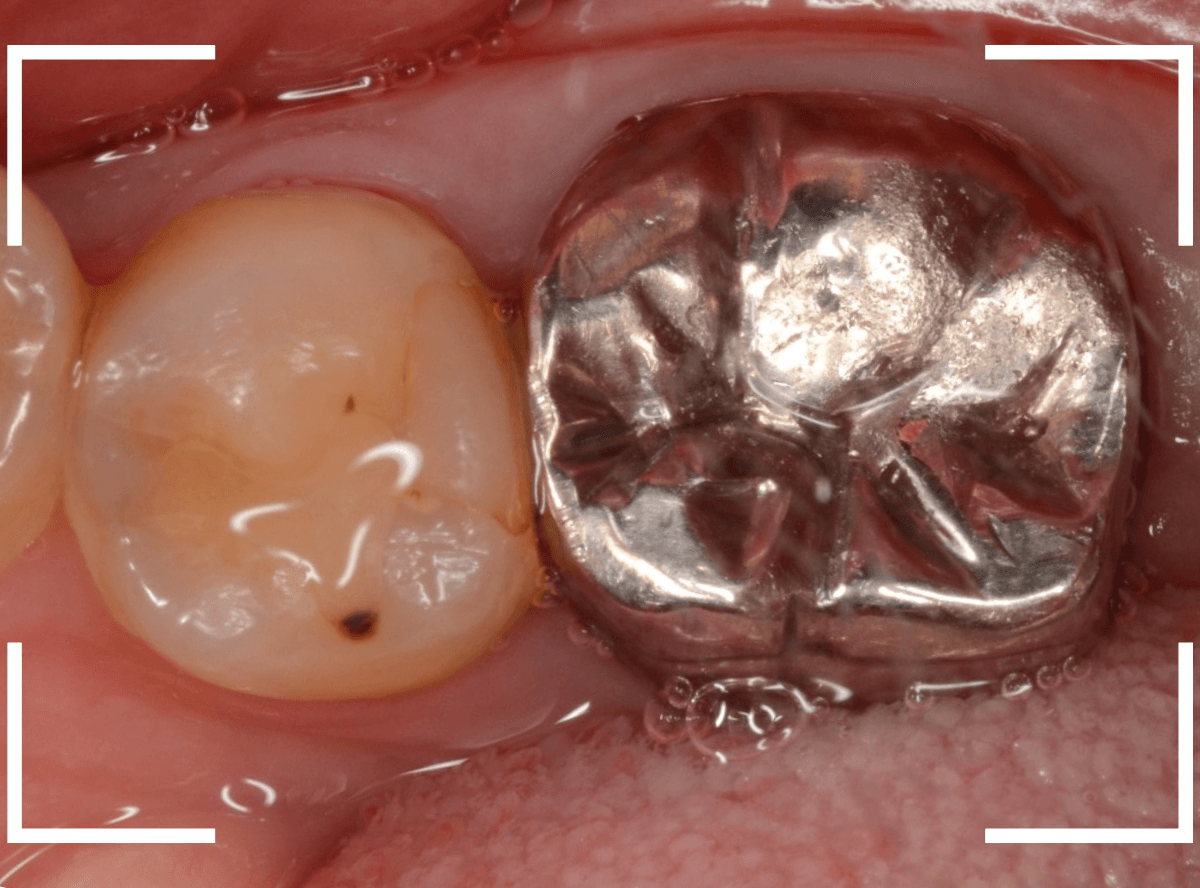

Case.19 メタル・クラウン、除去・再治療後、オール・ジルコニア・クラウンへ 4

今回は、上の奥歯の銀歯(メタル・クラウン)の中で虫歯になってしまった方です。

通常は、さし歯の中が虫歯になってしまうと、レントゲンにも写らず見つけづらいのですが・・・。

歯を裏側から見たところです。

幸い、見える部分に虫歯が

さし歯と歯肉の間に虫歯ができているのがわかります。

歯の奥まで虫歯が進んでいるのか、浅い虫歯ですんでいるのかは治療をしながら調べていく必要があります。

さし歯を外すと、金属の土台(メタル・コア)が出てきました。